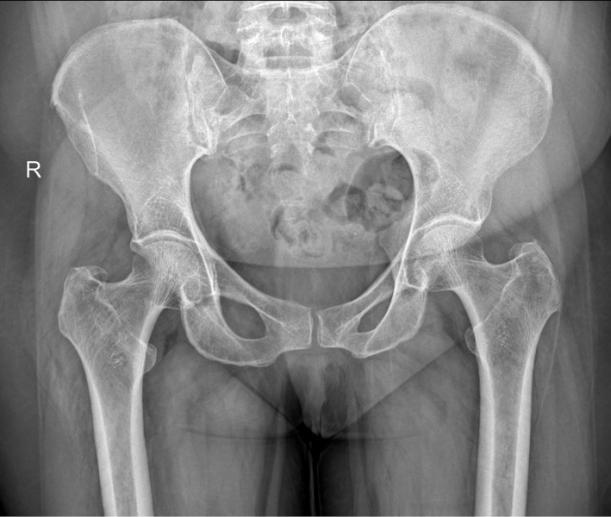

Au sein du Centre Lille Genou Hanche, le rôle du chirurgien consiste avant tout à réaliser un bilan approfondi, combinant examen clinique, analyse de la dynamique corporelle et imagerie. La tendinopathie du moyen fessier, parfois appelée tendinite du fessier, peut être confondue avec d'autres pathologies de la hanche, ce qui impose une évaluation précise pour identifier la source réelle de la douleur. L'examen tient compte de la qualité des muscles fessiers, de la position du bassin, d’éventuels troubles biomécaniques, ou encore d’une inégalité de longueur des membres pouvant favoriser des compensations.

Certaines formes, dites résistantes, touchent des patients présentant une évolution longue, un temps de guérison prolongé ou une pathologie associée, comme une atteinte tendineuse sévère ou une bursite chronique. Dans ces situations, le chirurgien peut recommander une approche plus avancée. Selon le cas, un traitement conservateur personnalisé est proposé, ou un geste chirurgical, comme la chirurgie de la tendinite du moyen fessier ou la réparation sous arthroscopie. Ces interventions visent à restaurer l’intégrité des tissus et à soulager durablement les douleurs.

Lorsque la tendinite évolue vers une forme sévère de la pathologie, que la douleur de la hanche persiste malgré la thérapie manuelle, la rééducation ou l'infiltration, la chirurgie peut devenir une option efficace. Les chirurgiens du Centre Lille Genou Hanche, cabinet de chirurgie orthopédique à Marcq-en-Barœul, évaluent alors la qualité du tendon, la présence d’une rupture partielle ou complète, et l'état des structures voisines.